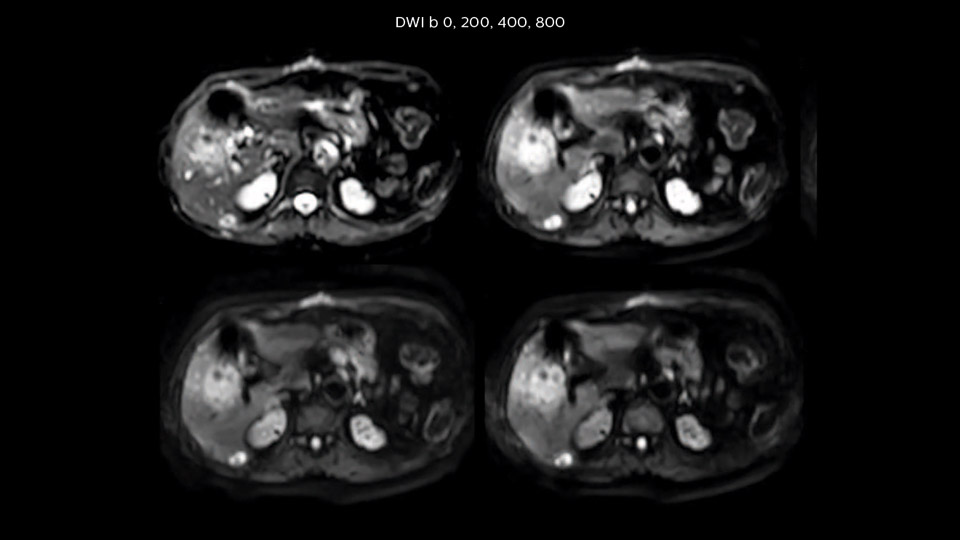

Comparison of liver MRI with and without MultiVane XD motion correction

In this example the image quality of the MultiVane XD images is evidently better than in the images without MultiVane XD. Ingenia 1.5T with dS Torso coil solution.

“We acquire one transversal high resolution T2-weighted sequence with 3 mm slice thickness, for example for pancreas or liver lesions. Then we also add a T2 fat suppressed MultiVane XD SPIR sequence. We perform these two routinely in our liver imaging. We use high dS SENSE factors to significantly shorten scan times to 2-4 minutes, which can improve our protocol; it’s a very robust scan.”